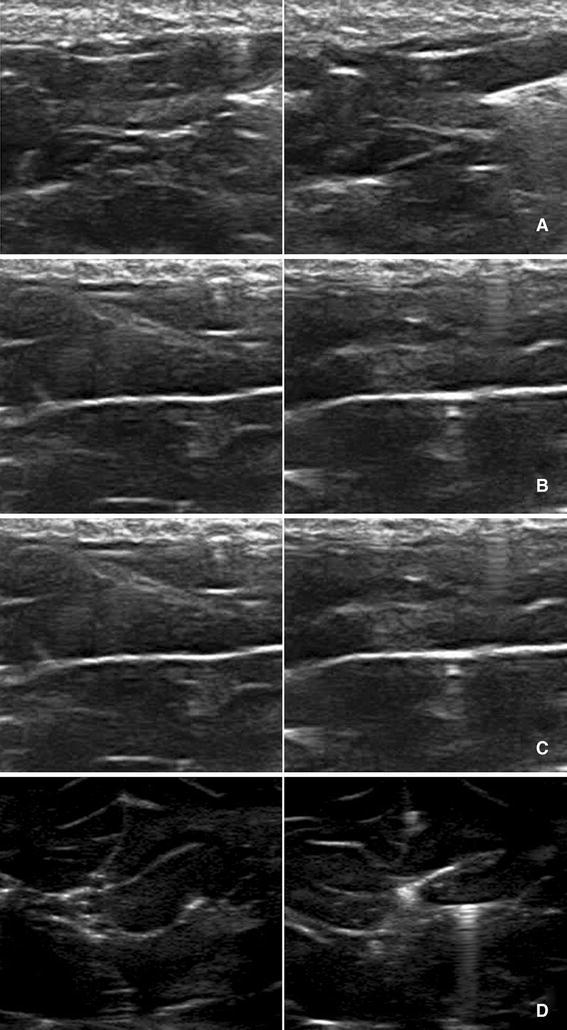

As seen in Fig. 1, all layers of animal model (i.e. fat plus skin layer, porcine brain tissue, plastic holder wall) were clearly depicted. Figure 2a, b, c shows the same echogenicity of porcine brain before and after injections of iron-loaded ferritin (a), apoferritin (b) and water (c). We were unable to notice any change in tissue echogenicity except subtle transient distortions caused by liquid flow, which were the same as typical for any liquid infusion. No stable change was observed.

Fig. 2.

a Left plain animal model. Right same model after ferritin injection. Injection needle can be seen. b Left plain animal model. Right same model after apoferritin injection on the right. Injection needle can be seen. c Left plain animal model. Right same model after water injection. d Left plain animal model. Right same model with glioma inserted. Needle (see interference pattern) marked tissue insertion. Hyperechogenicity compared to plain model can be clearly seen

On the other hand, in the second part of our experiment a marked hyperechogenicity in the area of glioma sample insertion was noticed (Fig. 2d). There was no significant difference between GII and GIV samples.